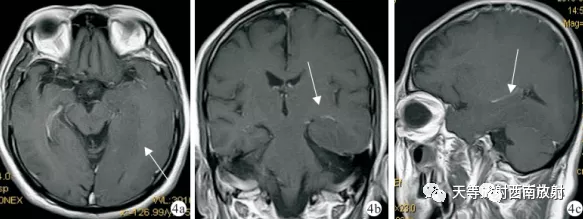

▲病例上图 MRI 增强 4a. 4b. 4c. 矢状位 T1WI病灶基本无强化,病灶边界仍不清楚(白箭)图 5a-b 患者病理像 镜下可见各种类型不同分化程度的纤维型胶质细胞在神经束间、神经细胞及血管周围弥漫浸润,胶质瘤细胞 呈类圆形或长条形,大小不一,多数细胞体积偏小,细胞浆量少,少部分增大,细胞核形态多种多样,未见出血、瘤团形成,可见坏死 区 5a. HE×20 5b. HE×40。(图3-5来源:黎本丰,钟凯,罗林.等.大脑胶质瘤病一例[J].华西医学,2013,28(9):1480-1480.)